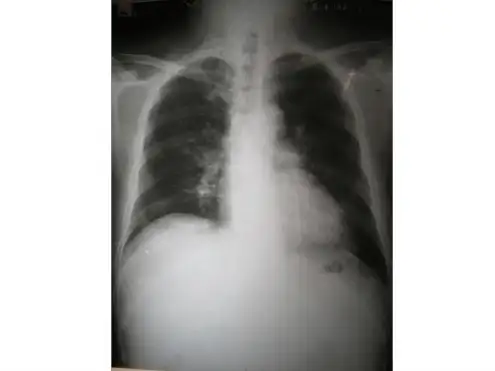

病毒性肺炎胸部CT片

让我们来看一下肺炎的X线影像学特征。

在早期阶段,肺炎的X线表现为肺纹理增多、模糊,随着病情的进展,会出现斑片状、絮状阴影。

在实变期,病变区域会出现密度均匀、边界清晰的阴影,有时可见空洞形成。

在消散期,阴影逐渐变淡,最终恢复正常。

值得注意的是,不同类型的肺炎在X线影像上有一定的特点。

例如,细菌性肺炎多表现为实变影,而病毒性肺炎则多表现为间质性肺炎。

三、性肺炎的影像学表现⒈ X线胸片表现性肺炎在X线胸片上的表现通常为两肺散在小斑片状或网状模糊阴影,病变范围广泛,密度较淡。

性肺炎还可表现为双肺多发斑片状、结节状或实体阴影,并且呈现对称性分布。

二、影像学检查。

胸部X线或CT检查对于病毒性肺炎的诊断具有重要意义。

病毒性肺炎的影像学表现常常是双肺散在斑片状浸润影,部分病例可伴有肺实变。

需要注意的是,病毒性肺炎的影像学表现与细菌性肺炎有所不同,结合临床表现进行综合分析有助于诊断。